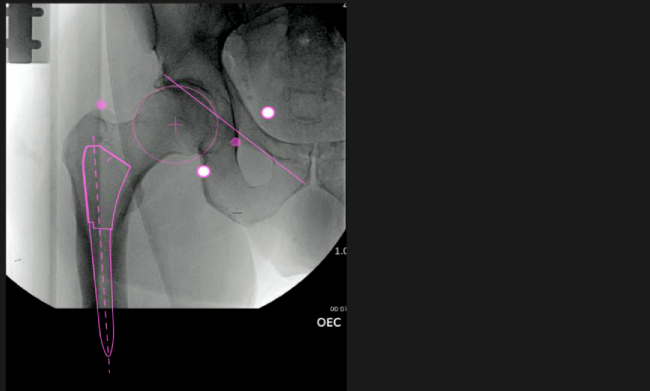

Planeación preoperatoria mediante la creación de plantillas digitales para reemplazo de cadera y análisis intraoperatorio

Mayor nivel de información intraoperatoria facilita la colocación correcta de los implantes:

Desplazamiento y offset para posicionamiento óptimo del componente (vástago) femoral.

Verificación de la posición deseada del implante que potencialmente puede ayudar a reducir la probabilidad de dislocación protésica y aumentar la estabilidad de la articulación.